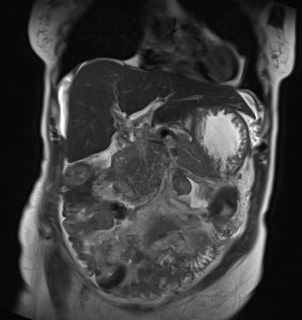

Так трапилося, що цю пацієнтку на шляху до діагнозу ще спіткали МРТ живота і таза (окремі візуалізації). Для зацікавленості пару картинок тут долучено, але погортати все МРТ детально можна тут - спочатку живота, а потім і тазу.

Цікаво, чи змінили ви ваше враження та думку щодо найбільш імовірного діагнозу після перегляду цих даних. Дайте нам знати в коментарях, якщо так сталося.